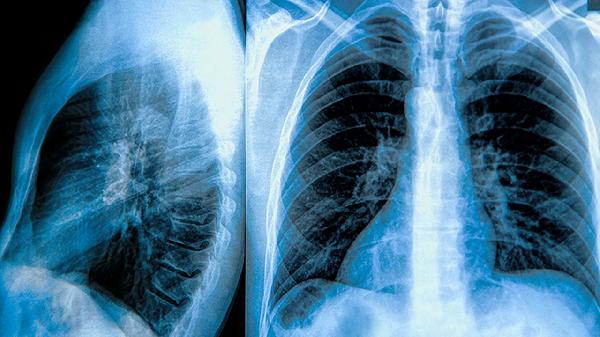

肺气肿和肺大泡不会传染。它们都属于非感染性的肺部疾病,肺气肿是慢性阻塞性肺病的一种表现形式,而肺大泡则是由肺泡结构受损后形成的囊状空腔。因为没有病原体存在,所以不会有传播风险。